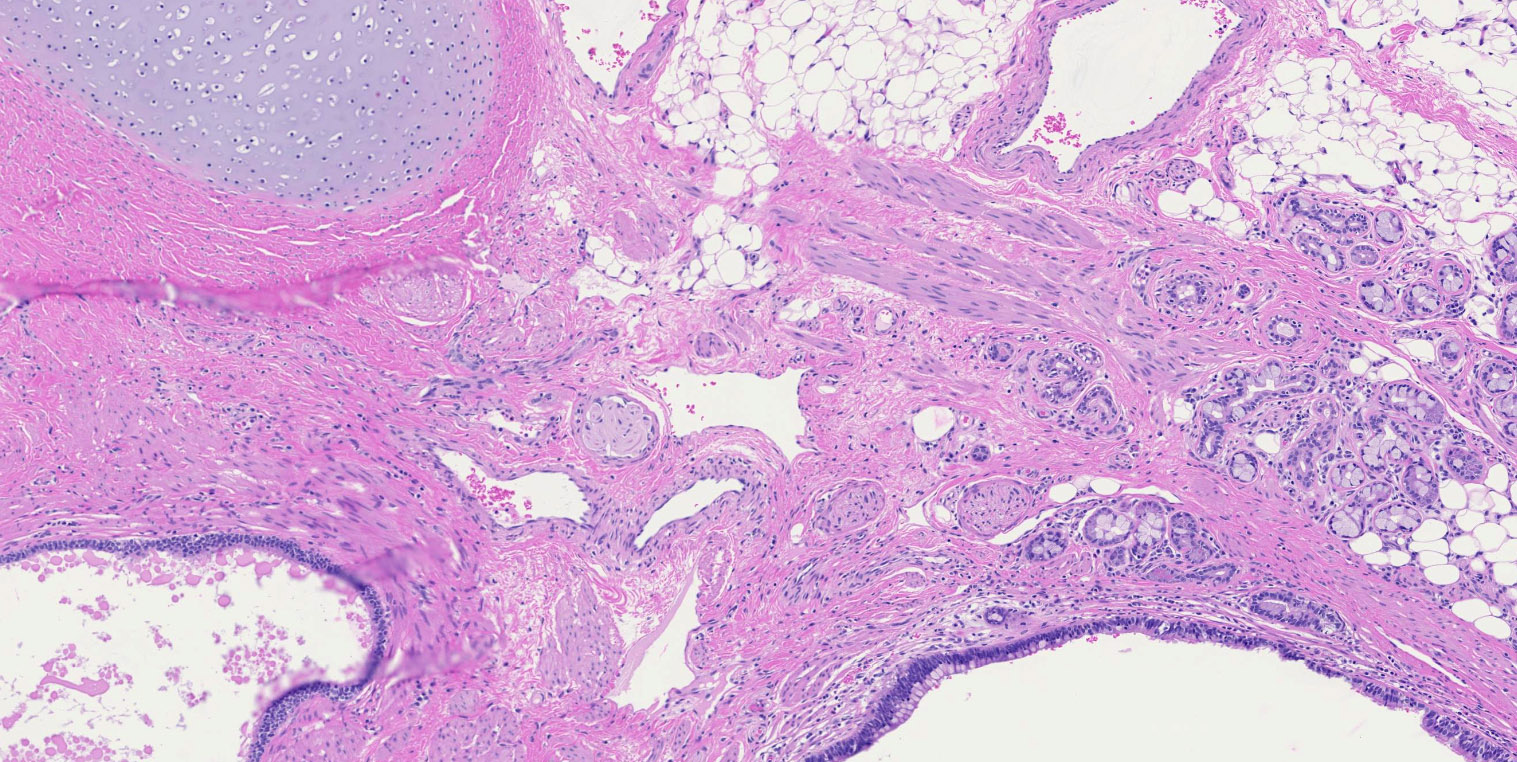

- Mixture of mature, benign tissues

- Ectodermal (most common): squamous epithelium, sebaceous glands, hair follicles, brain tissue

- Mesodermal (second most common): bone, cartilage, smooth muscle, fibroadipose tissue

- Endodermal: intestinal or respiratory epithelium, thyroid, salivary gland

Microscopic (histologic) images